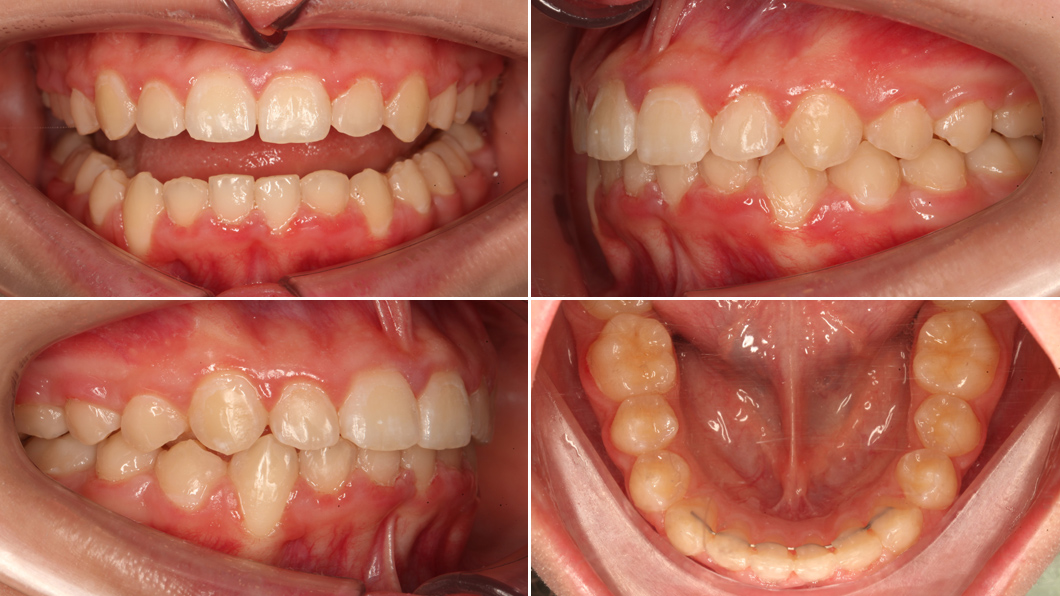

Для пациентки В. была выбрана несъёмная брекет-система. Этот метод даёт максимальный контроль над положением каждого зуба и позволяет эффективно устранить скученность, выровнять зубные ряды и установить правильные контакты между верхними и нижними зубами.

Лечение длилось около 2 лет. За это время с помощью брекетов были устранены давление и теснота, зубы заняли правильные позиции в широкой ровной дуге, нормализовано смыкание – верхние и нижние резцы начали контактировать правильно, без травмирующего давления. Процесс патологической стираемости был остановлен. Этапы лечения включали период адаптации, регулярные активации у врача, тщательную гигиену.

Лечение было проведено в самый подходящий период, что обеспечило стабильность результата и здоровье зубочелюстной системы на долгие годы: